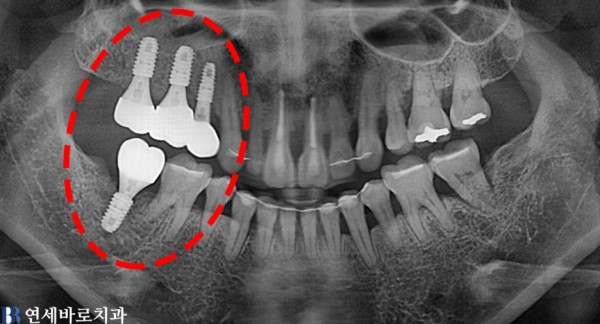

노화가 진행됨에 따라 잇몸병과 치주질환으로 인해

어금니가 흔들려 내원을 하셨습니다.

치료를 해야 할곳이 여럿 있지만 우선적으로 급한 곳 부터

임플란트 치료를 진행을 하였으며, 총 4개의 임플란트를 식립하여

오른쪽(사진상은 왼쪽)을 식사를 하실수 있게 원래의 상태로 회복 하였습니다.

(촬영시기: 전:22.10.12 후:23.04.05)